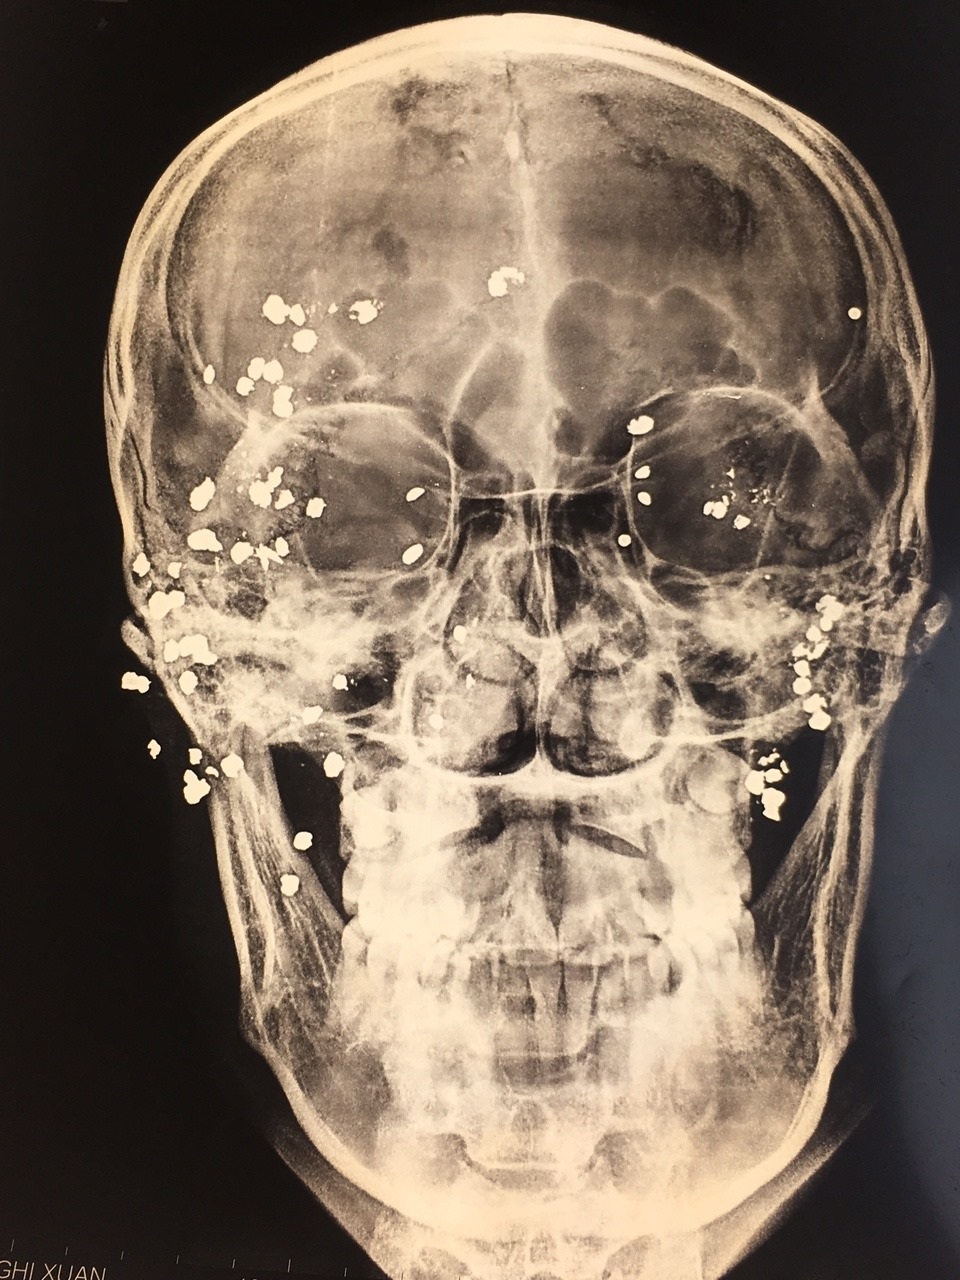

Những viên đạn "loé sáng" dưới hình ảnh chụp X- quang.

Sau khi tiến hành chụp X-quang và CT sọ não cho bệnh nhân, các bác sĩ phát hiện chi chít dị vật cản quang ở hàm mặt và hốc mắt 2 bên của bệnh nhân.